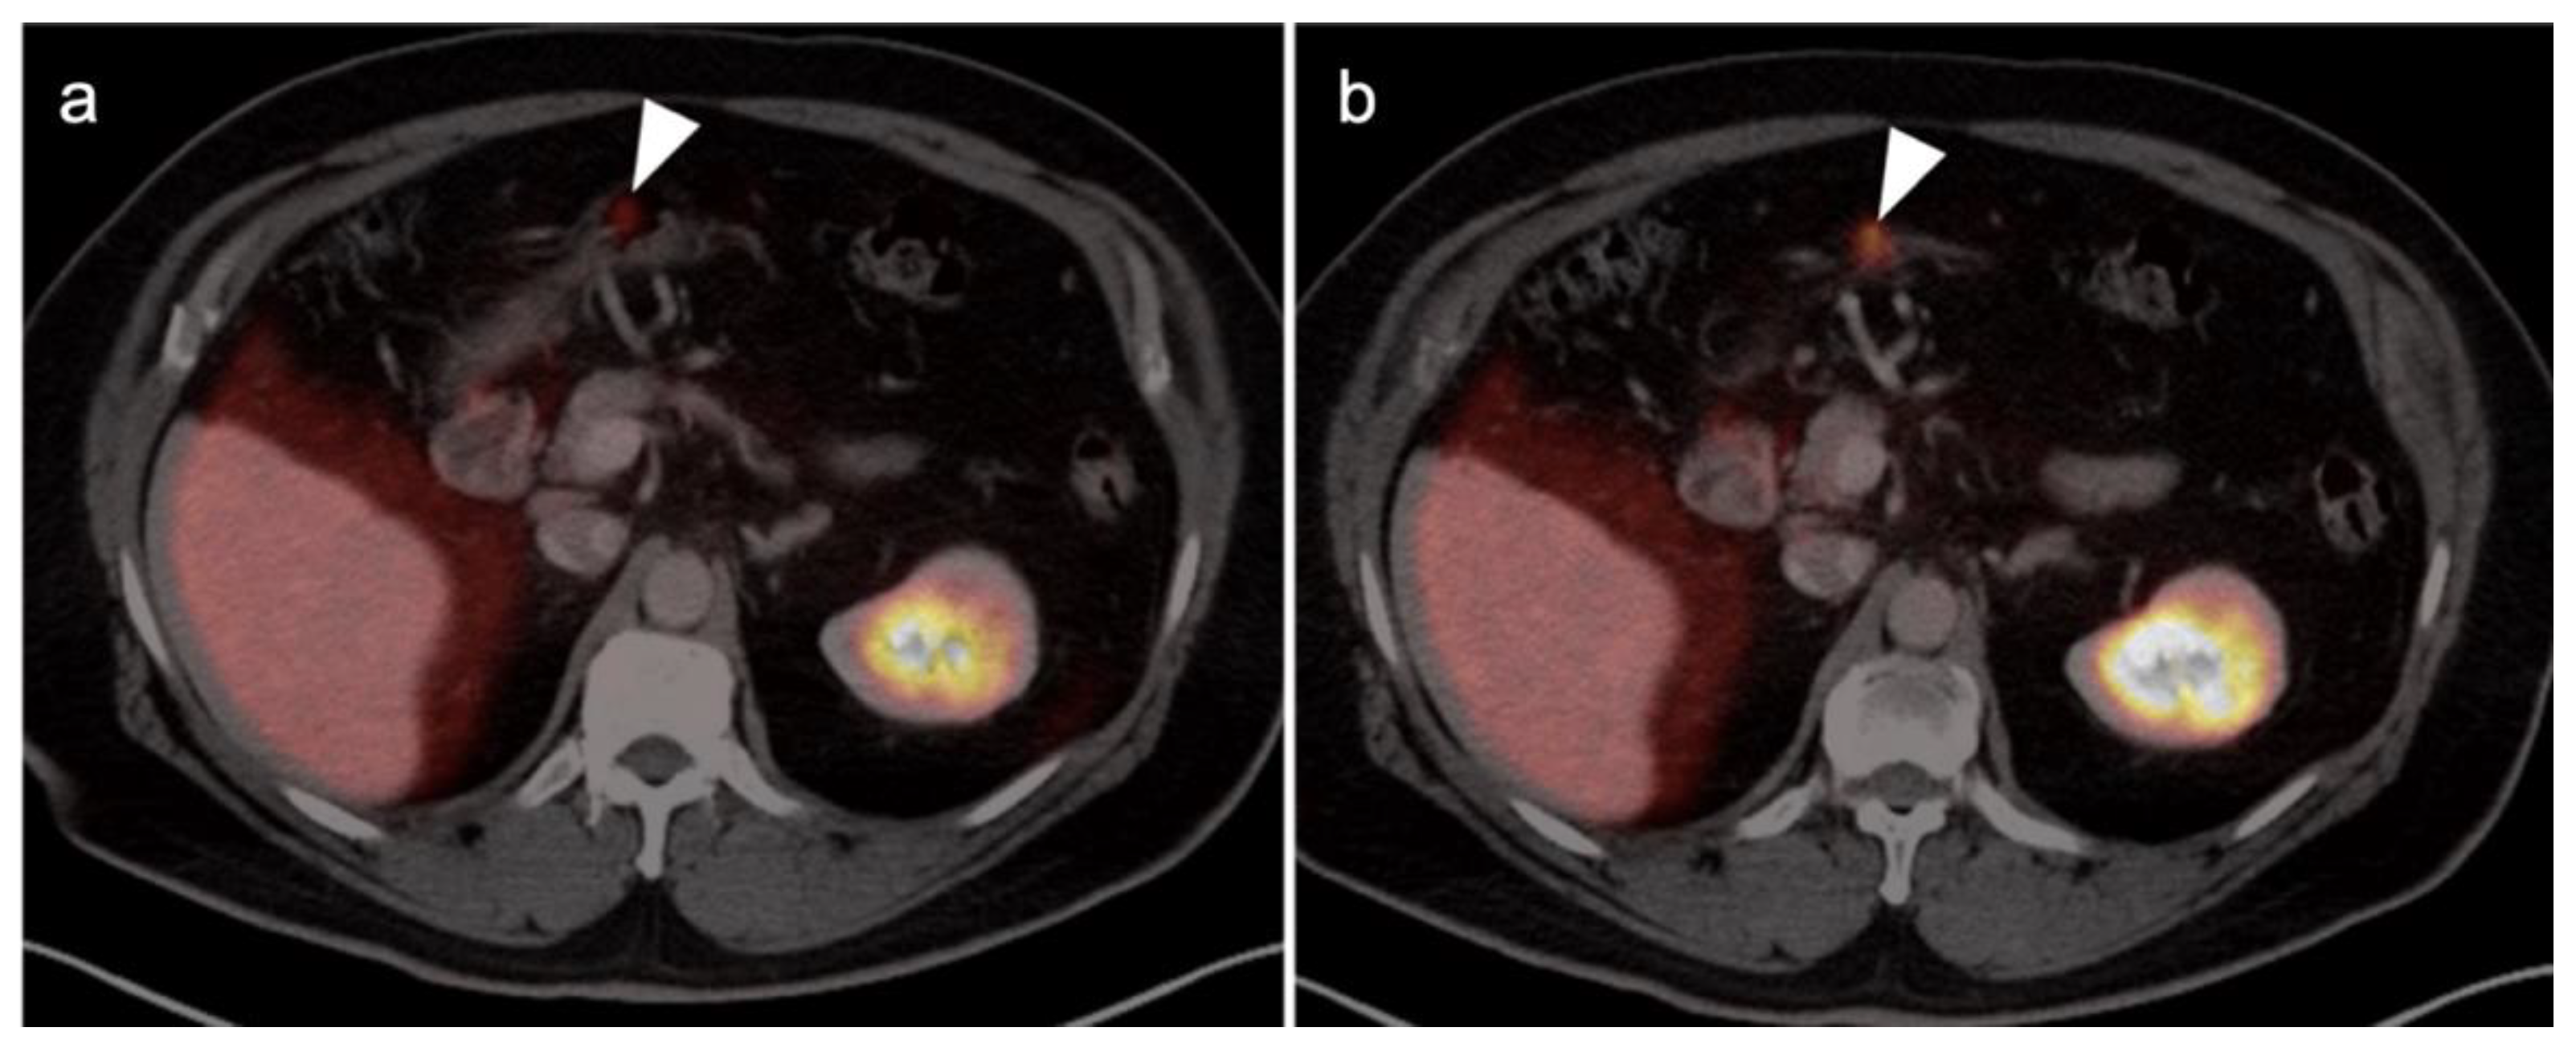

Abstract

3.1. Prostate Cancer

3.2. Urothelial Carcinoma